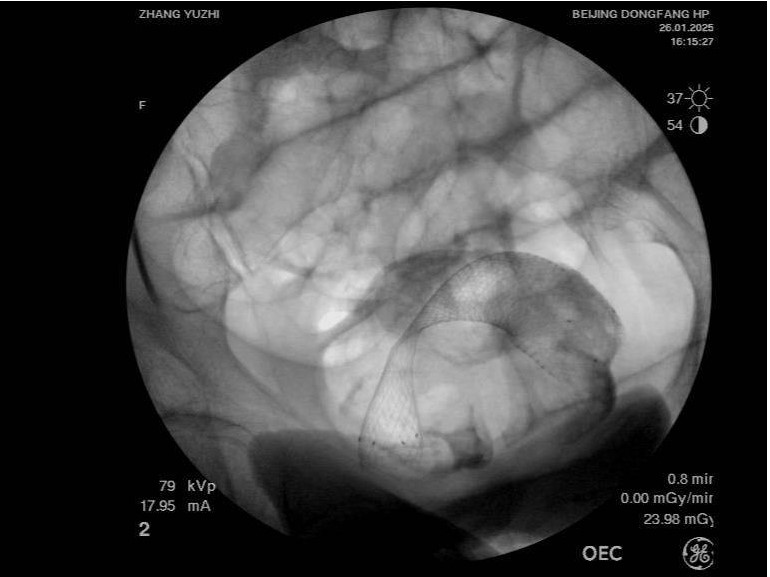

術后,患者的腹脹痛癥狀迅速得到緩解,很快恢復了排氣排便。第二天,患者就能正常進食米湯,飲食逐步向流食過渡。目前,患者病情平穩,已經轉入方莊院區外科接受后續治療。

治療前腹CT示腸腔明顯擴張 治療后立位腹平片示腸道梗阻較前明顯緩解